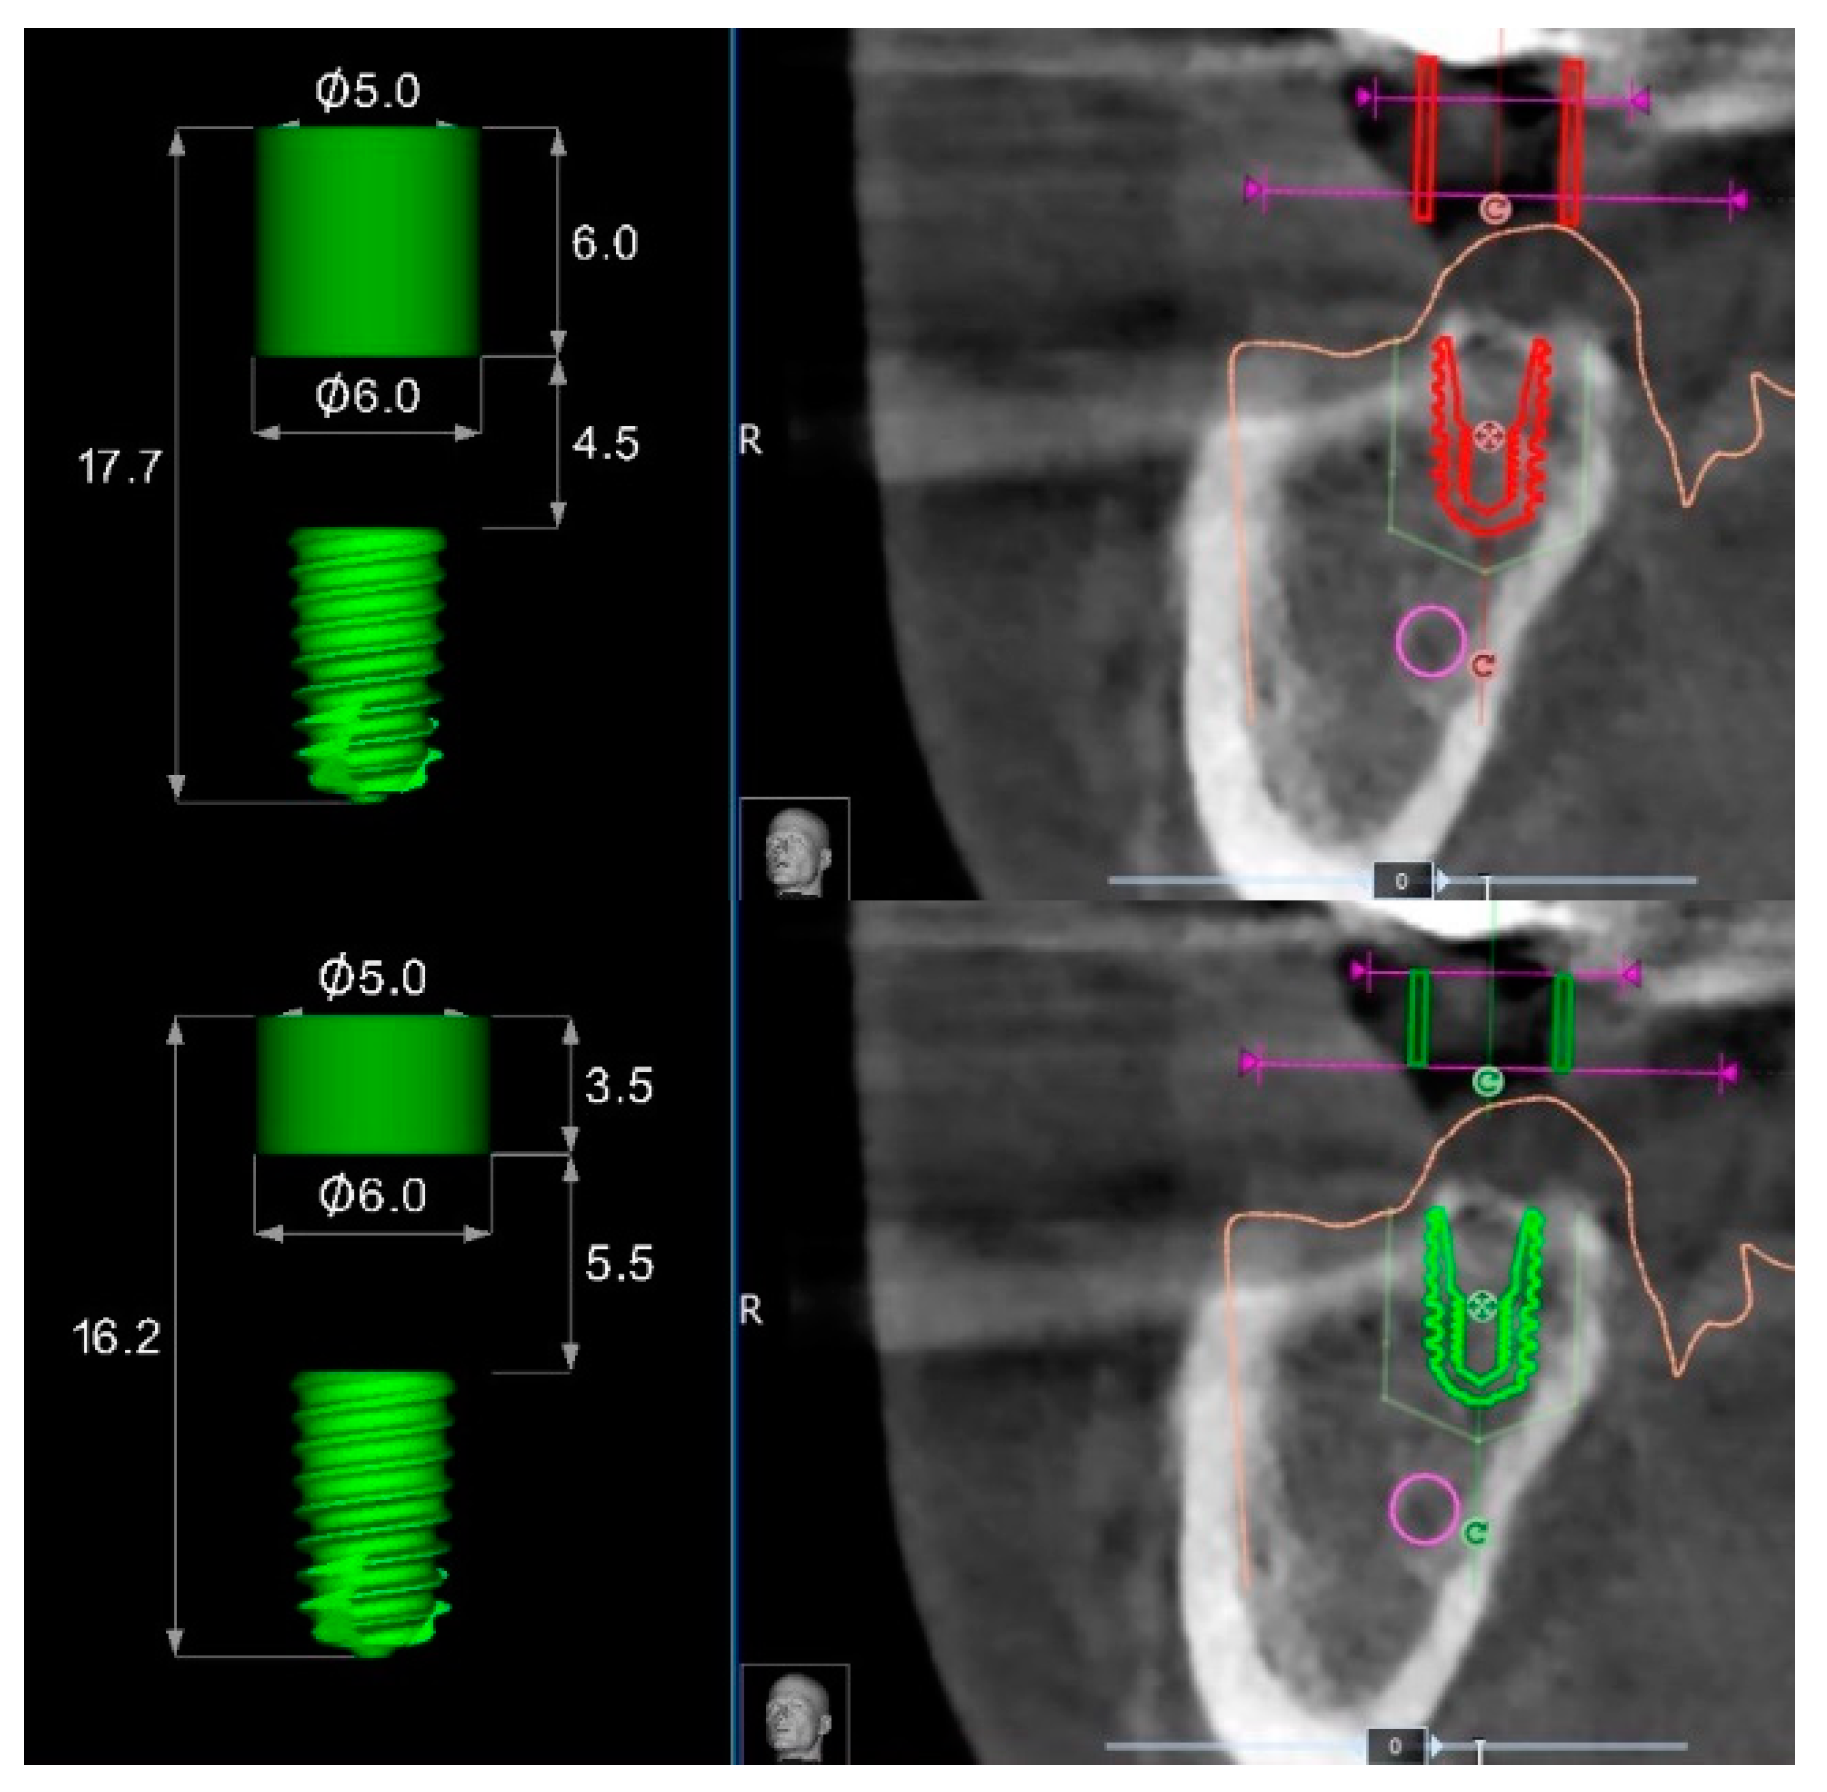

Accordingly, in the templates without metallic sleeves, the contact points between the template and the surgical drills with the entire space between the soft tissue and the templets results in a longer guide compared to the 3.5 mm of standard metallic sleeves, plus 1 mm of the metallic reduction (Figure 8) in case of templates with metallic sleeves. This difference should allow for larger and more stable contact between the surgical template and the guided drills during the implant site development, slightly reducing the overall wobbling of the guided drills. Indeed, a longer guiding channel was found to reduce the angular deviations of implants in an in vitro investigation [9]. Lastly, the implant mount drivers used in combination with surgical templates designed without metallic sleeves (NoMount Driver and Fixture Driver, OneGuide Kit, Osstem) are designed without any stop drill to the surgical guide. A stop drill should touch the surgical template on the side, creating a high pressure on the template that could generate a distortion of the same template, resulting in a reduction of the final implant accuracy [7]. Another benefit of the surgical templates designed without metallic sleeves was the reduced mesio-distal space. In fact, the metallic tubes have a thickness of 0.5 mm, which could make it impossible for their use in the case of narrow mesio-distal distance, such as in case of lower incisor or upper lateral incisors. In this case, the manual insertion of the implant after removing the surgical template is required.

Figure 8. Differences between surgical templates with (lower) and without (upper) metallic sleeves for a regular diameter implant of 7 mm length.